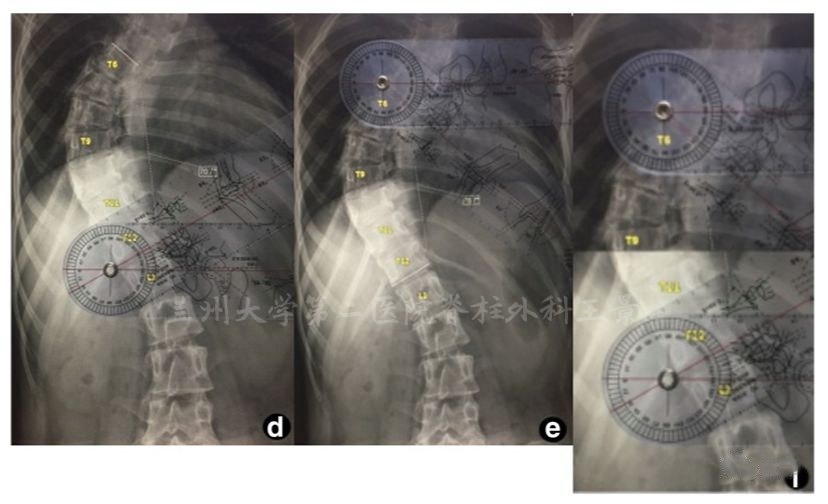

实际操作中的快捷方法

量角器底边放胶片上摆平

角度刻度线与端椎终板吻合后直接读数

水平线都不用画了,几秒钟时间

这种利用端椎倾斜角度的测量原理

可以用在手机上更直接快速的测量Cobb角